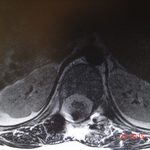

Εικ. 2: Προεγχειρητική αξονική τομογραφία του 12ου θωρακικού σπονδύλου (Εγκαρσια τομή)

Παρατηρείται ευμεγέθης εξεργασία στα οπίσθια στοιχεία του Θ12 σπονδύλου κυρίως δεξιά.